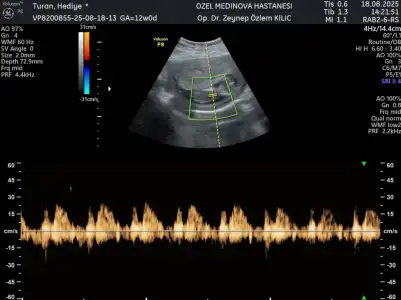

13+4 cinsiyet tahmini yapabilir misiniz

• 361F1037-0679-4857-9516-BA889BAB4F1C.webp

361F1037-0679-4857-9516-BA889BAB4F1C.webp

22,2 KB · Görüntüleme: 21